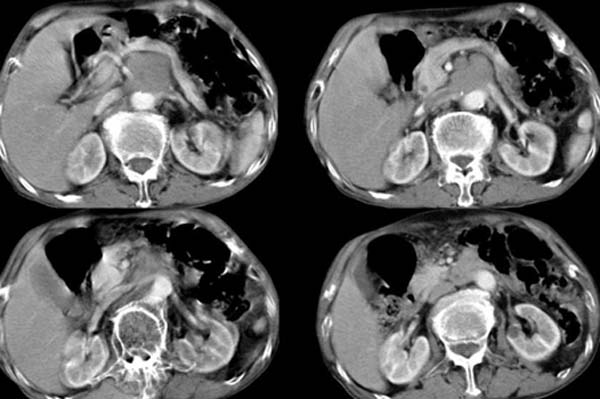

以下是引用zsl6918在2008-4-12 22:27:00的发言:[br]肝内未见异常密度灶,脾脏大小如常,腹主动脉旁可见一肿大淋巴结影,密度均匀,未见明显坏死表现。腹腔干被包绕,但未见明显侵犯,胃腔充盈尚可,未见明显占位表现。胰腺显示良好,略示前方移位。考虑腹膜后淋巴瘤可能性大。依据,转移瘤多有坏死表现,且有恶性肿瘤病史。第二,淋巴瘤未经治疗很少出现坏死表现,此点符合。第三,腹膜后其他肿瘤已经发现一般较大,本病例结节大小符合肿大淋巴结的表现。故首先考虑淋巴瘤。建议临床进一步检查其他部位的情况,另外结合实验室检查,注意病人有无贫血及低热表现。